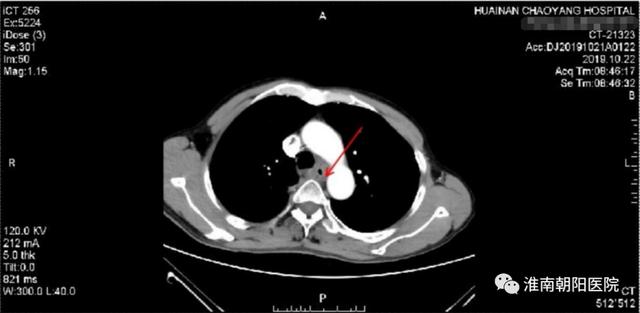

患者张大爷是一位来自寿县寿春镇的淳朴农民,2019 年 6 月初的一天,他吃饭时感觉明显梗噎疼痛感,症状越来越重。2019 年 8 月初去医院检查,通过胸部 CT 及胃镜等检查确诊为:「食管中上段鳞状细胞癌」。

(上图红色箭头就是食管肿瘤)